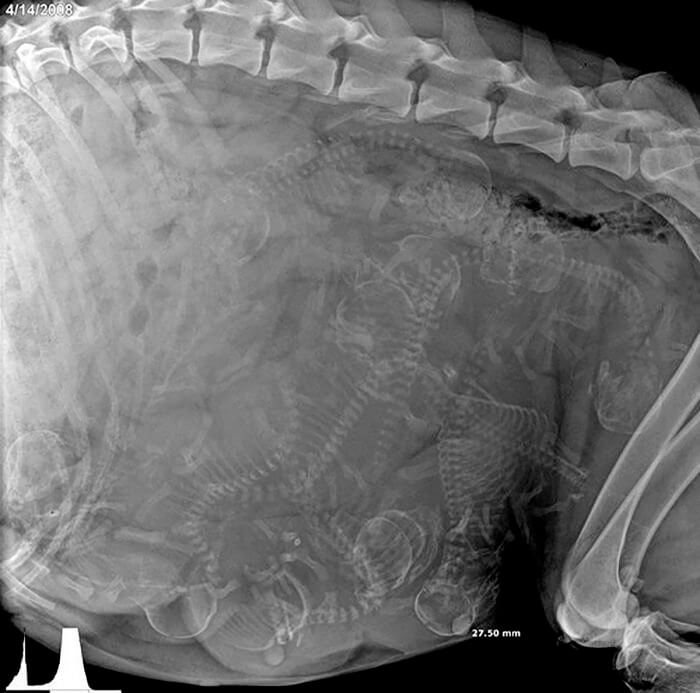

이 이미지에 제목이 없다면, 여러분의 생각은 큰 하나의 몸 안에 있는 수많은 작고 기괴한 이 해골들의 모습을 설명할 수 있는 가능성들로 미쳐버릴지도 모릅니다. 하지만 일단 여러분이 맥락을 이해하면, 이것은 실제로 생각하기에 꽤나 놀라운 일입니다. 이렇게 뼈들이 좁은 공간에 아주 많이 모여 있는데, 이것이 자연스럽다는 것이 충격적일 것입니다. 얼마나 많은 작은 강아지들이 곧 세상에 나올지 상상해보세요!

비록 사람들이 임신 초음파를 보는 것에 익숙하지만, 가끔 이런 개 같은 엑스레이 사진을 볼 때는 계속해서 충격을 받을 것입니다.